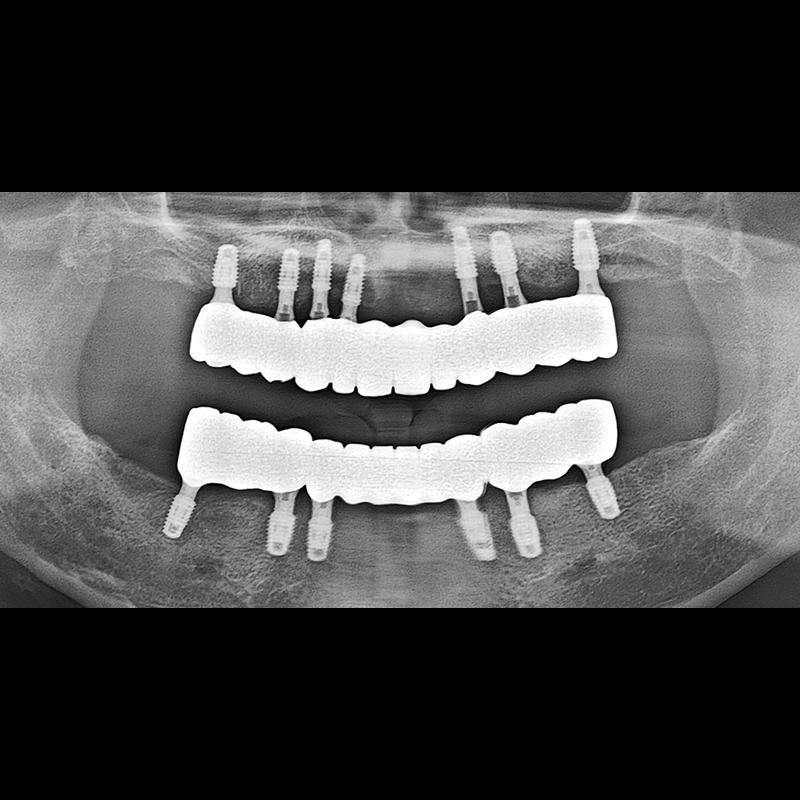

IMPLANT

BEFORE AFTER